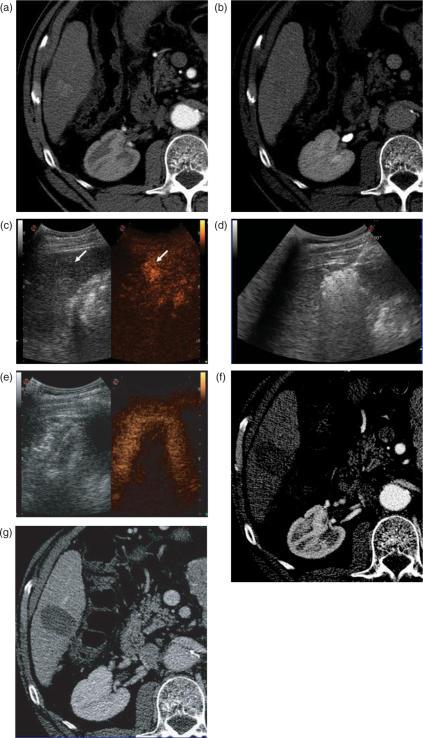

Hepatocellular carcinoma (HCC) is the fifth most common cause of cancer, and its incidence is increasing worldwide because of the dissemination of hepatitis B and C virus infection. Patients with cirrhosis are at the highest risk of developing HCC and should be monitored every 6 months to diagnose the tumour at an early, asymptomatic stage. Patients with early-stage HCC should be considered for any of the available curative therapies, including surgical resection, liver transplantation and percutaneous image-guided ablation. Liver transplantation is the only option that provides cure of both the tumour and the underlying chronic liver disease. However, the lack of sufficient liver donation greatly limits its applicability. Resection is the treatment of choice for HCC in non-cirrhotic patients, who account for about 5% of the cases in western countries. However, in patients with cirrhosis, candidates for resection have to be carefully selected to reduce the risk of postoperative liver failure. It has been shown that a normal bilirubin concentration and the absence of clinically significant portal hypertension are the best predictors of excellent outcomes after surgery. However, less than 5% of cirrhotic patients with HCC fit these criteria. Image-guided percutaneous ablation is the best therapeutic choice for non-surgical patients with early-stage HCC. While ethanol injection has been the seminal percutaneous technique, radiofrequency ablation has emerged as the most effective method for local tumour destruction and is currently used as the primary ablative modality at most institutions.